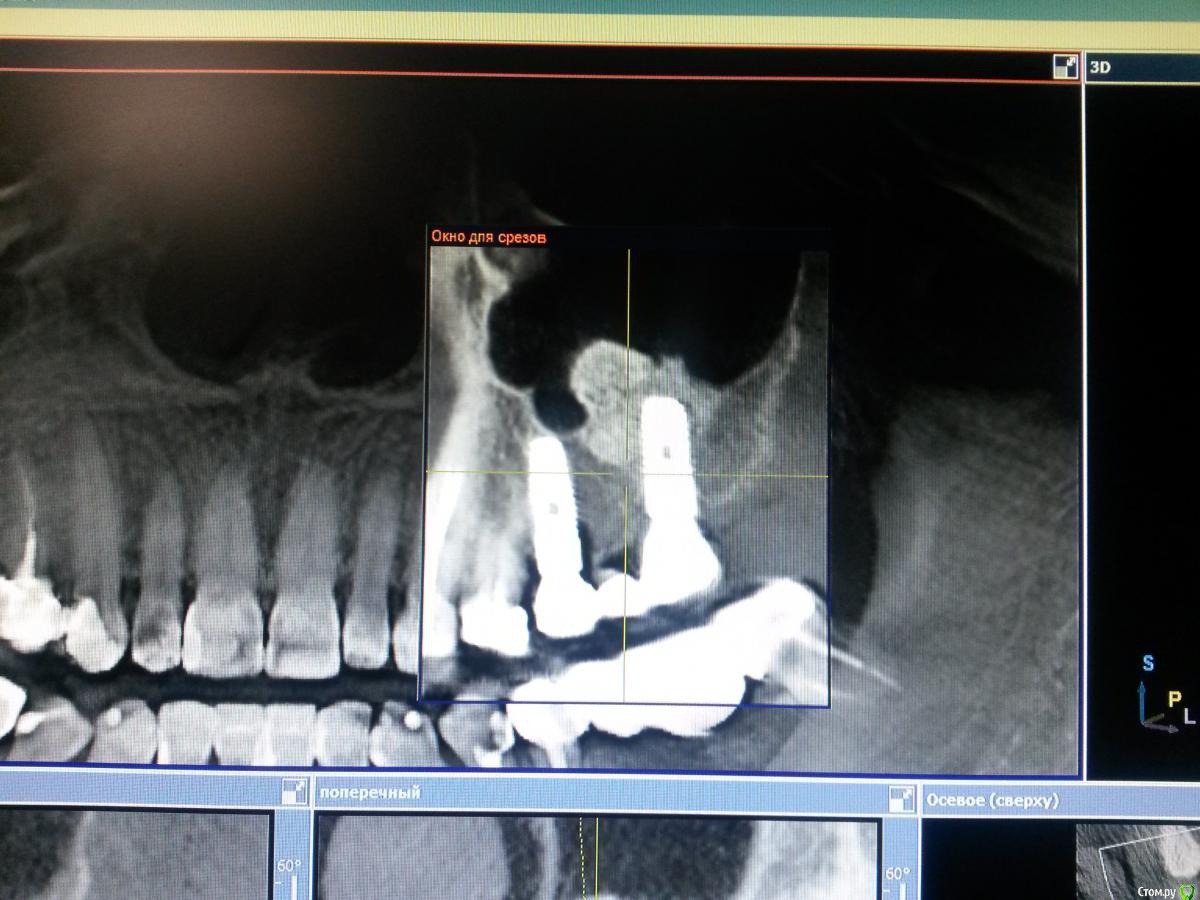

Nazim_NV86 Опубликовано 2 апреля, 2015 Поделиться Опубликовано 2 апреля, 2015 Оперирована 2г назад. Через полгода отпротезирована. Есть жалобы на периодическое жжение и нытьё. С периодами ремиссии и обострения. Со стороны СОПР всё в норме. Перкуссия отриц. Пальпаторно она сама не может понять где как и что. Во время операции ампутировал торчащий апекс 2.4. Была у 2 невропатологов. Бесполезно. Ссылка на комментарий

Nazim_NV86 Опубликовано 2 апреля, 2015 Автор Поделиться Опубликовано 2 апреля, 2015 Импланты Osstem Gs3. Bio-oss. Bio-gide. Ссылка на комментарий

Nazim_NV86 Опубликовано 3 апреля, 2015 Автор Поделиться Опубликовано 3 апреля, 2015 Подойдет Rg перед имплантацией.Когда появились жалобы? Связывает с чем-нибудь?Жалобы появились через месяц после операции. Вначале всё связывали с постоперационным синдромом. До операции КТ не было. Только ОПТГ. До ближайшего томографа 200км. Теперь уже у нас в городе их 3 шт. Этот Sirona. Ссылка на комментарий